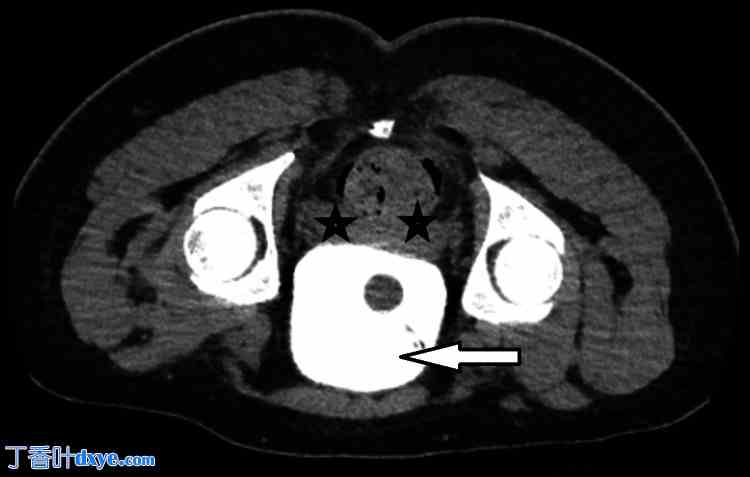

泌尿外科团队参与会诊,并同意采取保守治疗方案,留置导尿管 10 天。作者向患者解释了这一不幸的并发症,并根据 CT 检查结果,向他保证保守治疗即可。术后第5天(POD 5),引流管停止引流后,手术团队拔除了引流管,患者出院回家进行门诊随访,并计划于术后第10天(POD 10)拔除导尿管前进行复查CT膀胱造影。术后第10天,患者在门诊复查,并进行了CT膀胱造影。结果显示,膀胱充盈良好,导尿管球部位置正常,仰卧位和俯卧位均未见造影剂渗漏(如图3-4所示)。基于此,拔除了导尿管,一周后(POD 17)复查。患者恢复良好,伤口愈合良好,无泌尿系统问题,因此出院。

图3. 术后第10天CT膀胱造影轴位图像(仰卧位),显示膀胱内有造影剂(白色箭头),膀胱周围区域无造影剂渗漏(黑色星号)。

白色箭头:膀胱内充满造影剂,黑色星号:膀胱周围区域无造影剂渗漏